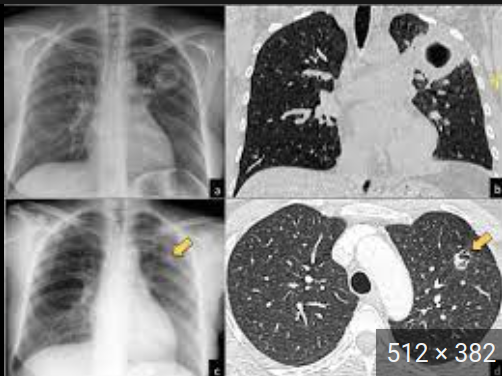

TBC Post-primaria o 2ria - Hallazgos radiologicos

La caverna tuberculosa la lesión fundamental.

Están rodeadas de zonas de consolidación y zonas de fibrosis en parches.

Evoluciona a un síndrome de retracción hemitorácica.

Afecta más frecuentemente a los segmentos apicales y posteriores de los lóbulos superiores, o los segmentos superiores de lóbulos inferiores.